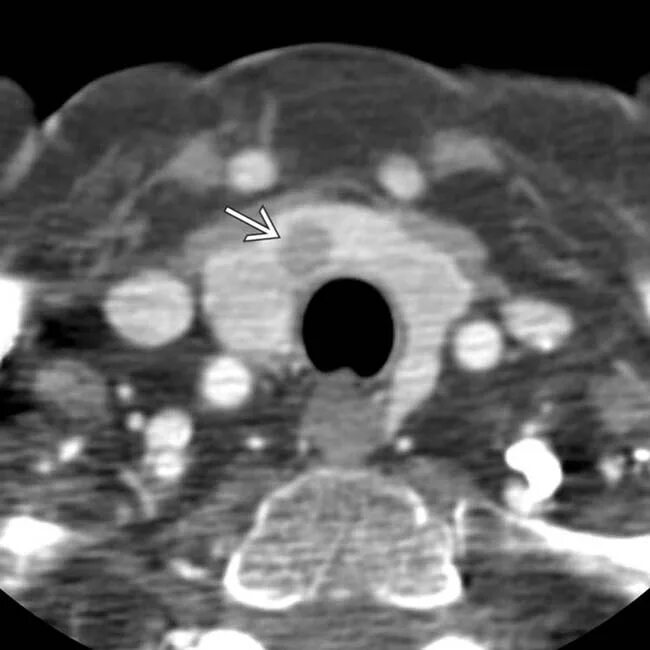

Симптом золлингера эллисона что это